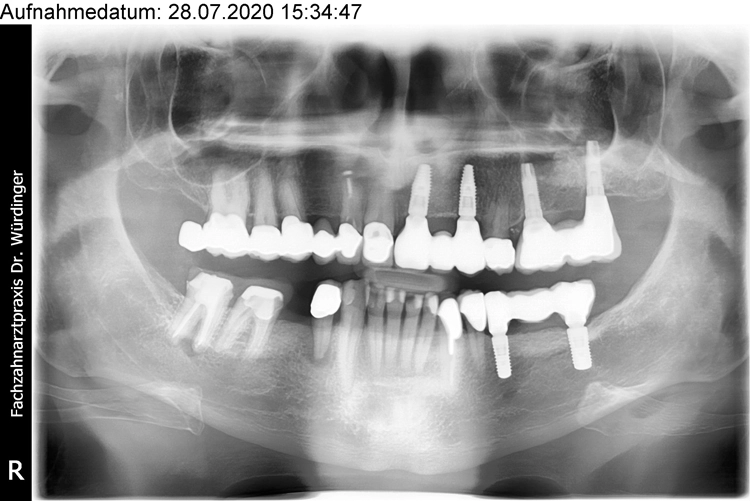

Ein 64 Jahre alter männlicher Patient ohne anamnestische Auffälligkeiten wurde mit dem Wunsch nach einer festsitzenden und ästhetisch ansprechenden Lösung im Frontzahnbereich von seinem Hauszahnarzt zur weiteren implantologischen Rehabilitation an unsere Praxis überwiesen. Nach eingehender klinischer Untersuchung wurde anhand einer 3D-Röntgenaufnahme mittels DVT das knöcherne Lager in der zu behandelnden Region beurteilt, worauf sich ein ausgeprägtes horizontales Knochendefizit zeigte, das eine Implantation in korrekter prothetischer Lage nicht zuließ (Abb. 1-3).

Die Entscheidung fiel daraufhin auf ein zweizeitiges Vorgehen mit vorheriger Knochenaugmentation in Schalentechnik und späterer Implantation von zwei BLT-Implantaten mit augmentativem Relining: Der Patient entschied sich nach ausführlicher Beratung und Vorstellung der alternativen Augmentationsmöglichkeiten für die Schalentechnik mit allogenen Kortikalisplatten und Granulaten (maxgraft® spongiosa, Straumann), wie die Abbildungen 4 bis 7 dokumentieren.